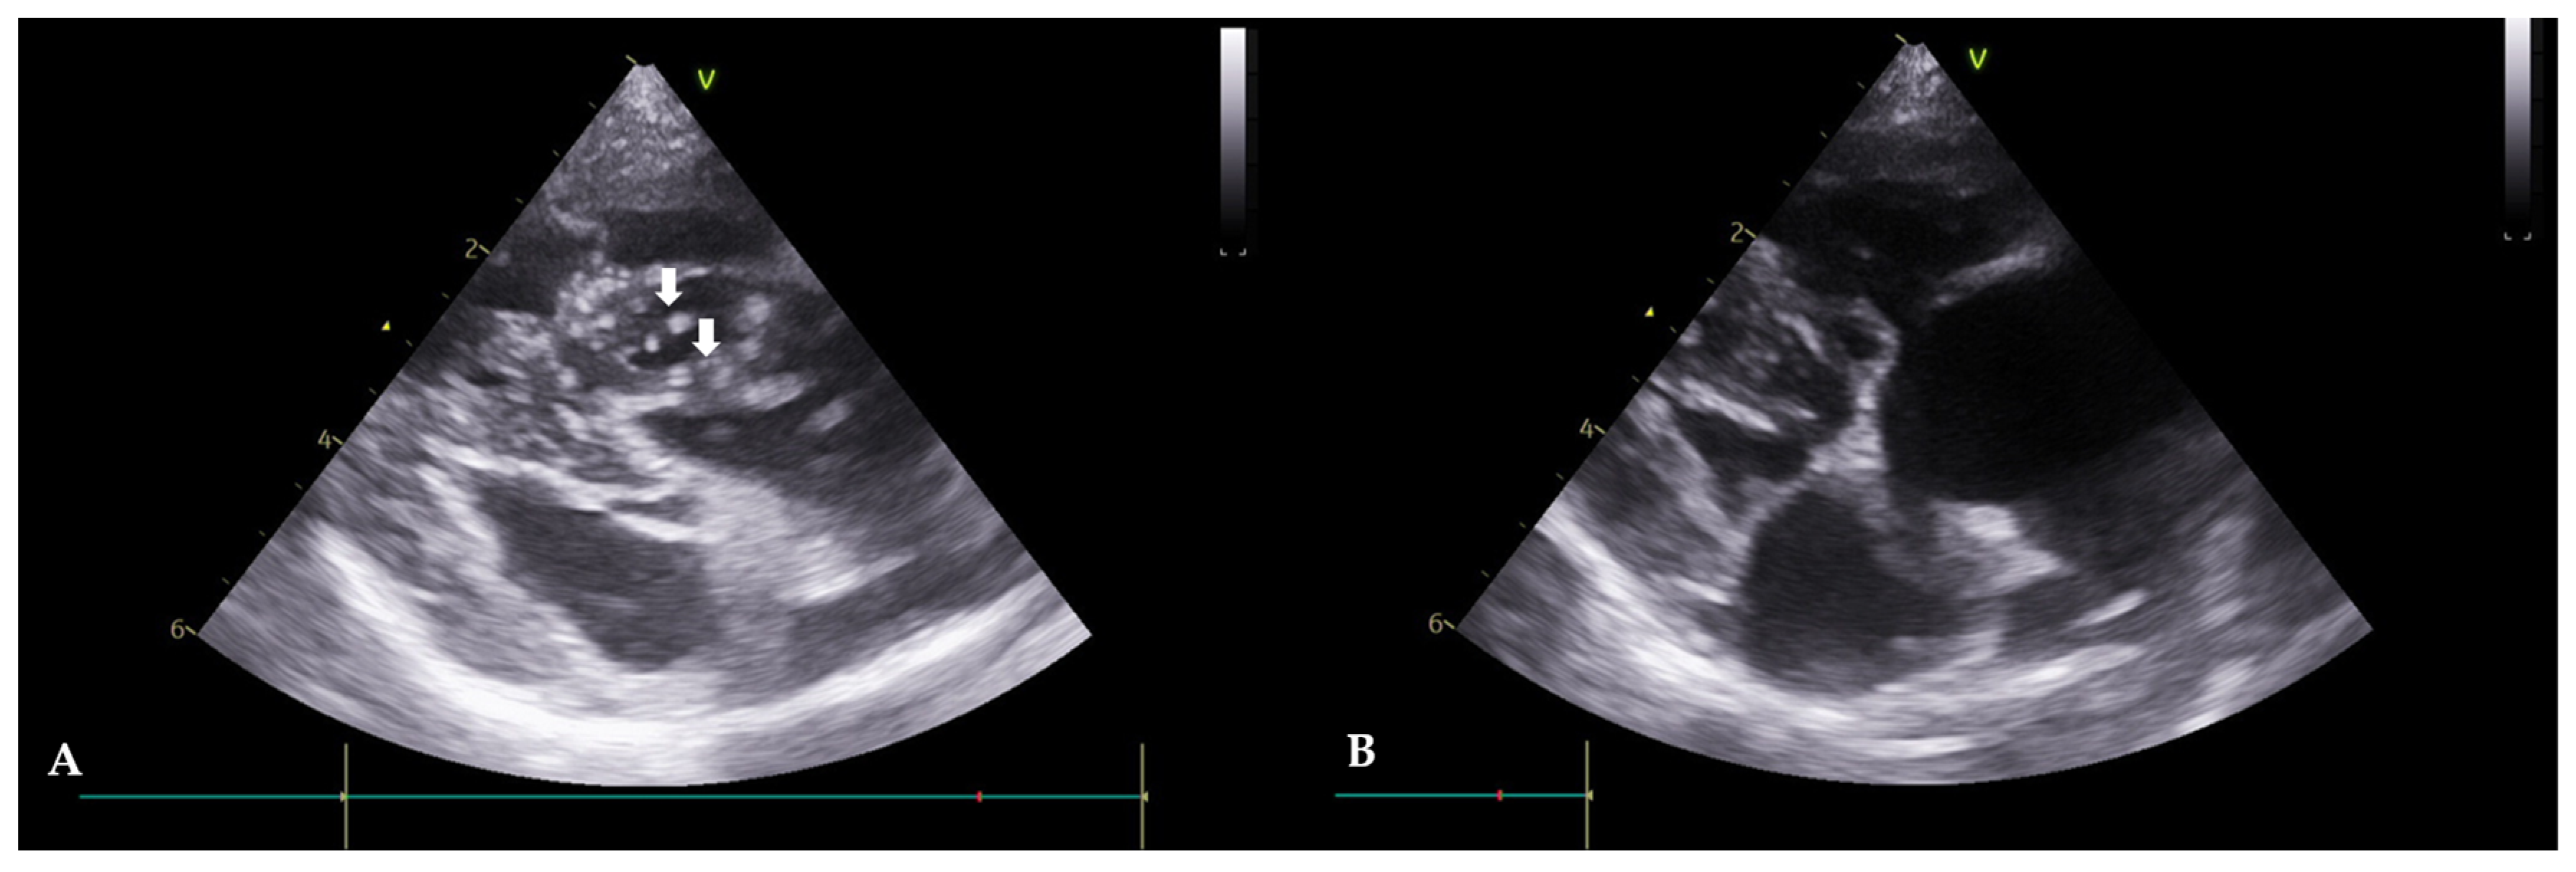

Figure 3. Echocardiograms of Case 2 before (A) and after (B) HW removal (right parasternal, short axis view). (A): Before the procedure, HWs are observed in the right atrium and ventricle (white arrows). (B): After the procedure, HWs are not observed.

A 13-year-old, spayed, female Yorkshire terrier, weighing 3.72 kg, was referred with symptoms of abdominal distension, anorexia, and tachypnea. In radiography, there was evidence of an enlargement of the left and right heart chambers, a reverse D heart shape (VHS 10.4), and a decreased visibility of the diaphragmatic line in the upper abdomen. The echocardiogram revealed HWs inside the right atrium, and severe tricuspid regurgitation was confirmed (Figure 3A). Mitral valve lesions were not identified. Moreover, color-flow Doppler imaging showed no evidence of mitral regurgitation. An immunological antigen test was positive for adult worms (Rapid CHW Ag 2.0 kit Bionote Co., Gyeonggi, Republic of Korea) and microfilaria was observed in the peripheral blood smear examination. The result of the abdominal fluid analysis showed a modified transudate. Seven days after the extraction, no further abdominal fluid was observed. Serologically, the liver enzymes were not elevated. However, there was an increase in WBC (18.7 × 103 cells/µL with a reference range of 6.0–17.0) and a slight azotemia (blood urea nitrogen, 43.6 mg/dL, with a ref. 9.2–29.2) was observed. To manage the right atrial dilation and improve the cardiac function, furosemide (1 mg/kg orally once daily; Lasix tablets, Handok Co., Seoul, Republic of Korea) and enalapril (0.5 mg/kg orally; Enaprin tablets, Jonggeundang Co., Seoul, Republic of Korea) were administered. After visiting the clinic, the patient took prescribed medication for three days to mitigate potential side effects before having the HW extraction. Subsequently, the HW extraction was performed as per protocol. Seven days after the intervention, adult HWs were not visualized on the echocardiograms (Figure 3B). The case included monitoring for pulmonary hypertension before and after the procedure using PV Vmax, TR Vmax, and TR max PG values. Before the procedure, the PV Vmax was 0.79 m/s, the PV max PG was 2.48 mmHg, the TR Vmax was 5.43 m/s, the TR max PG was 117.91 mmHg, the E peak velocity was 0.47 m/s, and the E/A Ratio was 0.78, and after the procedure, the PV Vmax was 0.68 m/s. The PV max PG was 1.87 mmHg, the TR Vmax was 4.16 m/s, the TR max PG was 69.25 mmHg, the E peak velocity was 0.73 m/s, and the E/A Ratio was 0.78. Pulmonary hypertension was still in the severe stage, but an improvement in the speed of TR Vmax was observed.